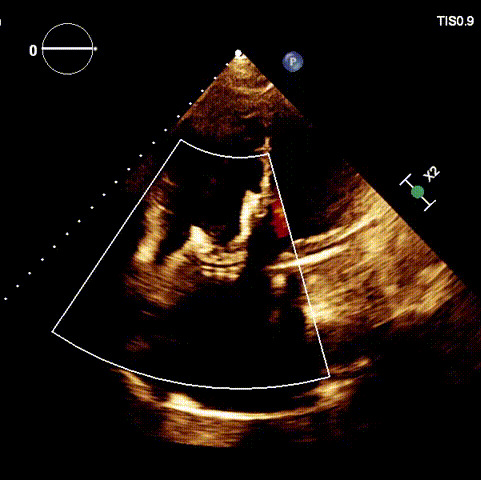

術(shù)后超聲

近日,廈門大學(xué)心血管病醫(yī)院王焱教授帶領(lǐng)的結(jié)構(gòu)性心臟病團(tuán)隊(duì),成功應(yīng)用LuX-Valve Plus經(jīng)血管三尖瓣置換系統(tǒng),為一例高危三尖瓣重度反流患者開展經(jīng)血管三尖瓣置換手術(shù)。此次手術(shù)系LuX-Valve Plus人工瓣膜在福建省的首例植入,手術(shù)過程順利,術(shù)后患者三尖瓣反流顯著改善,標(biāo)志著由葛均波院士團(tuán)隊(duì)作為主要研究者的LuX-Valve Plus經(jīng)血管三尖瓣置換系統(tǒng)全國(guó)多中心臨床研究的再一次成功實(shí)踐,為三尖瓣介入治療的醫(yī)學(xué)循證打下了夯實(shí)的基礎(chǔ)。 、